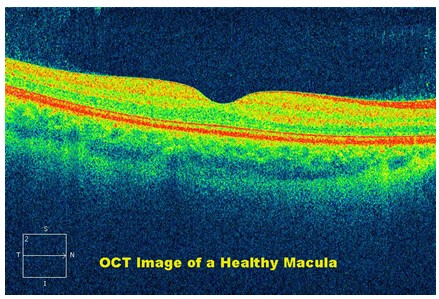

c. Optical Coherence Tomography

Optical coherence tomography (OCT) is a non-invasive imaging test that uses light waves to take cross-section pictures of your retina, the light-sensitive tissue lining the back of the eye.

With OCT, each of the retina’s distinctive layers can be seen, allowing mapping and measurement of their thickness. These measurements help with diagnosis and provide treatment guidance for glaucoma and retinal diseases, such as age-related macular degeneration and diabetic eye disease.

Macular Oedema in Diabetic Retinopathy